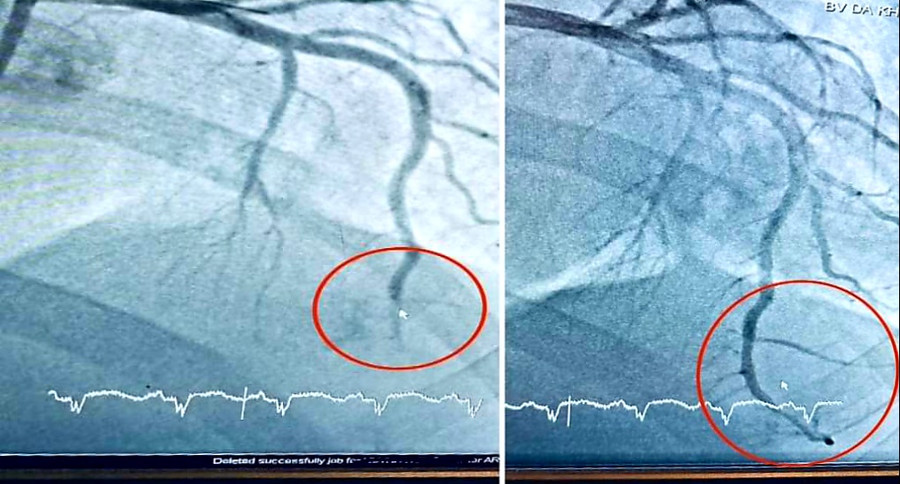

| Hình ảnh vị trí tắc động mạch liên thất trước và sau can thiệp. |

Khi chụp mạch, các bác sĩ phát hiện có tắc hoàn toàn động mạch liên thất trước đoạn xa (LAD3) với kích thước mạch máu lớn.

Bệnh nhân được đặt 1 stent mạch vành khẩn cấp.